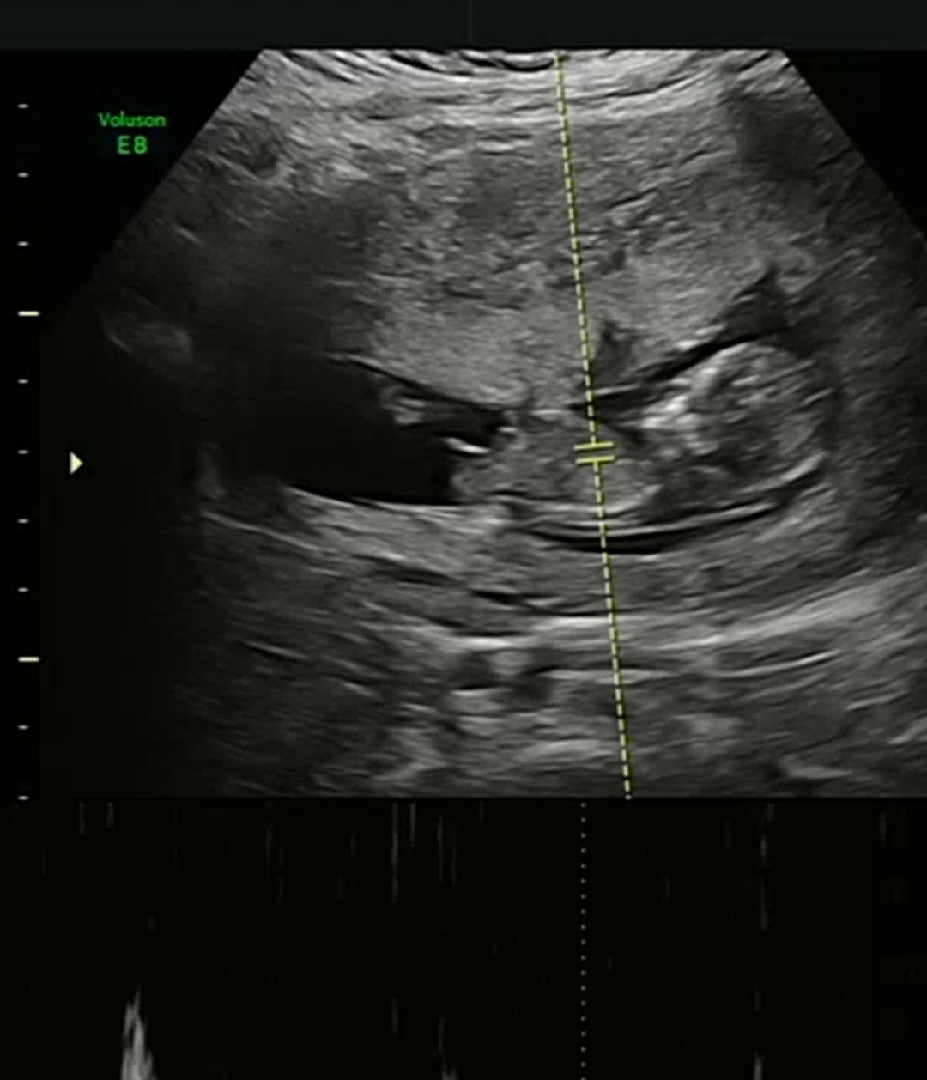

11주5일 지피티는 각도상 딸같다고했는데 딸이였으면한데 한번씩봐주세요ㅠ